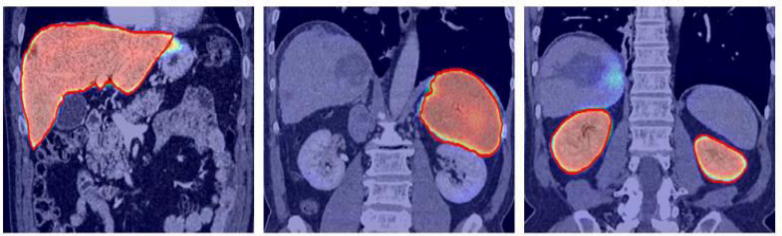

The objective of the project is to segment the organs and lables those organ in MRI Images.

Due to increase in a large dataset of human body MRI, it is tedious and time-consuming to segment each organ manually and then automatically analyze patient-specific organ. To make the process digitized computerized analysis of these images requires accurate segmentation of anatomical regions. The segmented images contain homogeneous, non-overlapping, semantically meaningful regions of the similar attribute. Classification is used to label each segmented organ. Intensity-based image segmentation is feasible when there is a large difference between the intensities of the object of interest and its background.

- Step 1: Data collection - In this phase different organ MRIs will be collected and labeled. It involves the collection of MRI of Kidney, Lung, Liver, Gallbladder, Pancreas, Spleen, Stomach

- Step 4: Training and Experimentation -In this stage , the pre-processed images will be feed as input to the network. After training, the network will be tested on other MRI images for segmentation